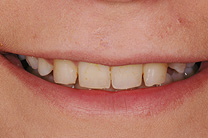

Fallbeispiel

Zum Vergrössern klicken